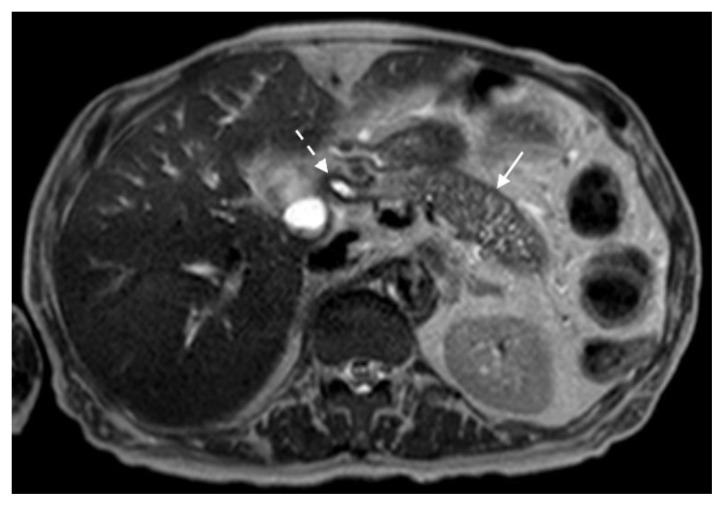

Figure 8.

78 year-old male with IgG4-related autoimmune disease.

Findings: T2-weighted MRI demonstrates loss of pancreatic parenchymal lobulations with peripheral soft tissue rind (solid arrow) seen throughout the pancreatic body and stricture at the proximal CBD (dashed arrow).

Technique: Axial T2-weighted. 1.5T, TR = 1000, TE = 80, 5 mm slice thickness.

The MRI revealed soft tissue encased the proximal common bile duct (CBD) and biliary hilum, resulting in a 4cm-long stricture, with increased upstream intrahepatic biliary dilatation (Figures 5, 6). The hepatic parenchyma demonstrated diffuse heterogeneous enhancement, without a focal mass or pseudotumor, consistent with inflammatory changes. The pancreas demonstrated parenchymal T2 hyperintensity and T1 hypointensity with diffuse enhancement, including an enhancing peripheral soft tissue rind, again consistent with autoimmune pancreatitis (Figure 7). The kidneys also demonstrated multifocal regions of abnormal enhancement and restricted diffusion (Figure 9, 10). Persistent enhancing soft tissue surrounding the SMA and IMA was again noted (Figure 11, 12).